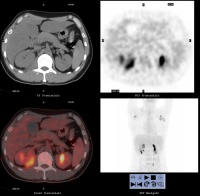

1.B超检查 方法灵活、准确、无创伤、可重复、价廉、易为众多患者接受,能准确地显示息肉的大小、位置、数量、囊壁的情况。B超典型的表现为胆囊壁有点状、小块状、片状的强或稍强回声光团,其后多无声影,可见到球状、桑葚状、乳头状及结节状突出,甚至可显示出息肉的蒂。杨汉良等报道B超对PLG检出率为92.7%,特异性94.8%,假阳性5.2%,准确性明显高于CT,认为BUS能清晰地显示PLG的部位、大小、数目及局部胆囊壁的变化,是一种简便可靠的诊断方法。

胆囊息肉三维超声成像

2.三维超声成像 可使胆囊具有空间方位的立体感,透声性好,有直视胆囊剖面的效果,可弥补二维显像某些不足。不仅可观察胆囊息肉的大小形态,更可分清息肉和胆囊壁的关系,尤其在胆囊后壁的息肉二维显像常不能清楚地分辨是否有蒂以及蒂与胆囊壁附着的范围和深度。三维重建能通过不同切面的旋转来观察病变的连续性及病变表面的情况等信息,有助于提高胆囊息肉与胆囊腺瘤或癌肿的鉴别。王连生等报道用三维超声成像检查18例胆囊内病变,最大直径为5.5cm,最小直径0.3cm,其中5例为多发性息肉,9例为单发性息肉,4例胆囊癌均为多发占位病变。三维超声成像与术中所见基本一致。

3.内镜超声(endoscopic ultrasonography,EUS) 即经内镜超声扫描,是将超声微小探头安置在内镜顶端,探头为高频,将内镜插入消化道,进入十二指肠壶腹后此探头更接近胆囊,可排除肠气干扰或胆汁黏稠度等影响。EUS可将胆囊壁分为3层,内层为高回声黏膜及黏膜下层,中层为低回声的肌纤维层,外层为高回声的浆膜下层及浆膜层。如为息肉样病变可见清晰的3层囊壁,而胆囊癌则囊壁的3层结构有不同程度的浸润破坏。早期胆囊癌绝大多数是在结石和息肉等病变的掩盖下发展的,早期缺乏特征性声像图表现,鉴别困难。而EUS检查观察息肉样病变与胆囊壁之关系,有助于鉴别诊断。朱燕陵等回顾分析了103例非结石性胆囊病变EUS检查结果并与体表超声及手术后病理进行比较,EUS检查诊断正确率为75%,体表超声为41.4%,EUS对胆囊息肉、胆囊癌、胆囊腺肌瘤诊断符合率为100%,体表超声为55.6%。Sugiyama认为内镜超声(EUS)比BUS更准确,提供的图像也更清晰。因194例PLG中,EUS判断的136例非肿瘤性病变平均随访2.6年均未发现肿瘤;而BUS判断的非肿瘤性病变中则有13%为肿瘤。EUS内层的回声方式为细小声点(tiny echonic spot)、声点聚集(aggregation of echogenic spot)、微小囊肿(microcyst)及彗星尾征(comet tailartifact)。如EUS证实既无细小声点与声点聚集,又无微小囊肿与彗星尾征时,应怀疑为腺瘤或癌肿。两者无法鉴别,除非已浸润至肝脏,但若为无蒂病变,则强烈提示为癌肿。结合组织学研究,一个细小声点表示一群含有胆固醇泡沫的组织细胞,而无回声区则为腺上皮增生。多个小囊肿和彗星尾征则分别为罗-阿窦增多和胆囊壁内结石所致。